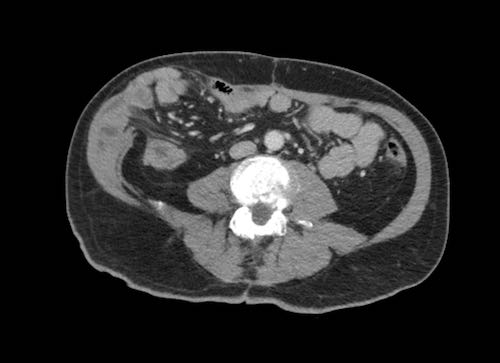

Hình ảnh

Các cấu trúc dạng tấm mỏng là hình ảnh mạc treo ruột dày nhẹ.

Ở đầu tận, một đoạn ruột non được gắn vào.

Trong trường hợp không có cổ trướng, sẽ không thể phát hiện được tình trạng dày tinh tế này.

Theo nguyên tắc chung, khả năng quan sát thấy mạc treo ruột là một dấu hiệu đáng lo ngại, đặc biệt khi có hình ảnh dạng nốt.

Trong trường hợp không có lượng lớn dịch cổ trướng, việc phát hiện tình trạng dày mạc treo ruột sẽ khó khăn hơn.

Cần tìm kiếm các tổn thương dạng nốt hoặc đường thẳng dày được bao quanh bởi mỡ ở phía mạc treo của ruột.